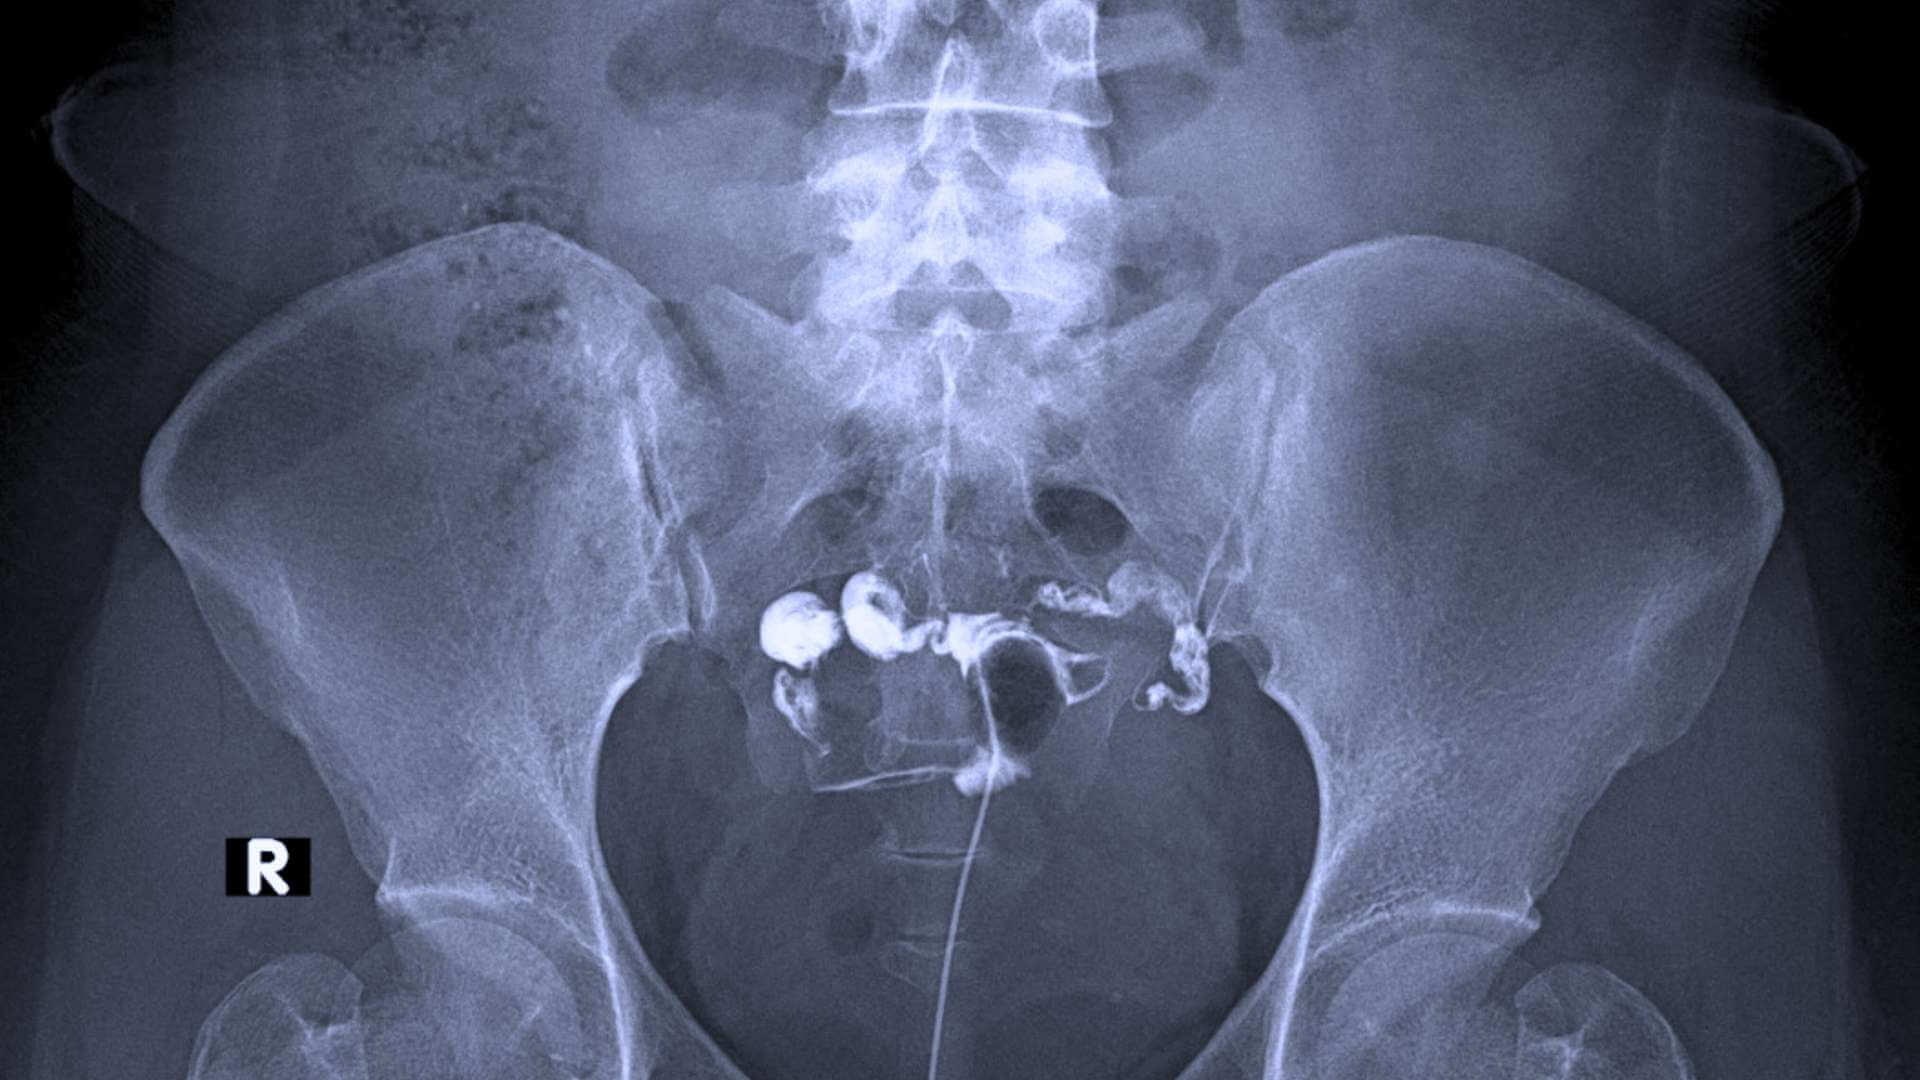

Hysterographie

Description de l’examen